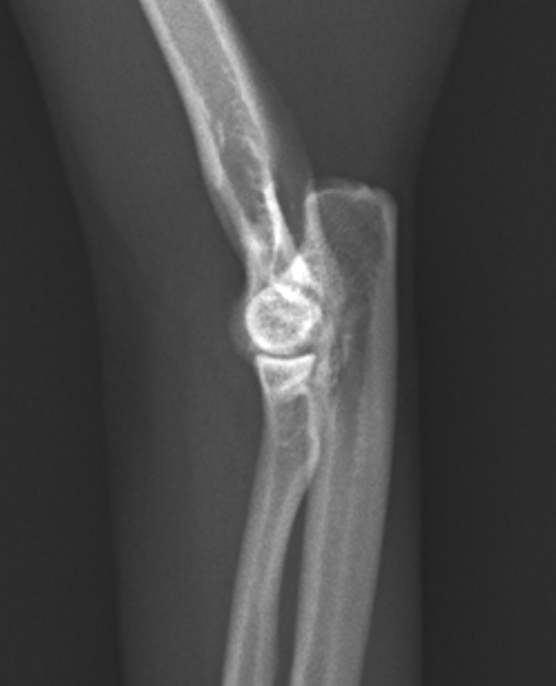

これは正常な方の前肢です。